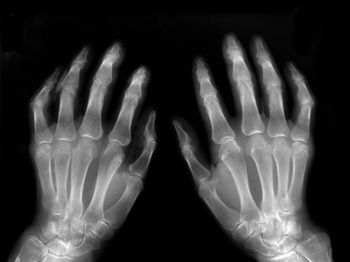

Opioid use among patients with rheumatoid arthritis is prevalent, and while there is a small decrease in overall opioid use after tumor necrosis factor (TNF) inhibitor initiation, newly initiated opioid use after TNF inhibitor initiation may reflect an unmet need in pain management, say researchers writing in Rheumatology and Therapy this month.